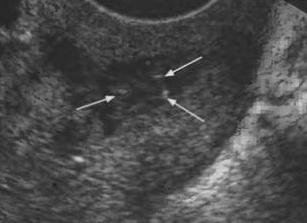

При правильном расположении гиперэхогенное включение доходит до дна полости матки и не выступает за пределы внутреннего зева. При использовании в качестве внутриматочного контрацептива петли Липпса, ультразвуковая картина характеризуется при поперечном сканировании обнаружением цельной гиперэхогенной линии и отдельных включений повышенной эхогенности при продольном. При перфорации матки внутриматочным контрацептивом определяется гиперэхогенное включение частично расположенное в толще миометрия. Чаще это происходит в области дна матки.

Хронический эндометрит. Данный процесс обусловлен гиперплазией эндометрия и может происходить в любой возрастной группе. Ультразвуковая картина гиперплазии вариабельная, чаще имеет вид гиперэхогенных включений небольшого размера (2-7 мм) с четкими контурами, неправильной формы, возможно расширение полости матки. У женщин репродуктивного возраста утолщение эндометрия и гиперэхогенные включения сохраняются во все фазы менструального цикла.

Полипы эндометрия. В большинстве случаев полипы имеют изоэхогенную структуру, однако если в структуре полипа большое количество нитей фибрина, то это приводит к повышению эхогенности образования. Фиброзные полипы имеют схожую ультразвуковую картину с эндометритом. Отличительными чертами является наличие четких ровных контуров, круглая форма при поперечном сканировании. Наблюдается нарушение смыкания листков слизистой, контуры его становятся волнистые, прерывистые. При цветовой допплерографии выявляется сосудистая ножка полипа, которая состоит из вновь образованных сосудов, питающих образование.

1. Пузырьки воздуха. Данные образования в просвете матки могут появляться в следствие выскабливания матки, а так же при длительном течении хронического эндометрита. При УЗИ визуализируется гиперэхогенное образование с четкими контурами, чаще множественные и небольшого размера. Иногда наблюдается акустический эффект «хвост кометы», который визуализируется как множество эхогенных полос позади образования.

2. Остатки плодного яйца. Эхографическая картина вариабельная и зависит от того, на котором произошло прерывание беременности. Если остались ткани хориона, то ультразвуковая картина характеризуется разнородностью структуры и повышенной эхогенности. Если прерывание беременности происходит на более поздних сроках, то фрагменты костных структур визуализируются в виде гиперэхогенных образований с четкими контурами и акустической тенью.

3. Гематометра. Сгустки крови в просвете матки могут оставаться после оперативного вмешательства или родоразрешения. При исследовании визуализируется увеличенная в размерах матка с гиперэхогенными неоднородными включениями без признаков кровотока при использовнии допплера. При УЗИ они имеют схожую картину с остатками хориона. При проведении дифференциальной диагностики важное значение принадлежит динамическому наблюдению. С течением времени сгустки крови подвергаются деструктивным изменениям и смещаются по отношению стенок матки. Компоненты хориона со временем свое строение и расположение практически не изменяют.